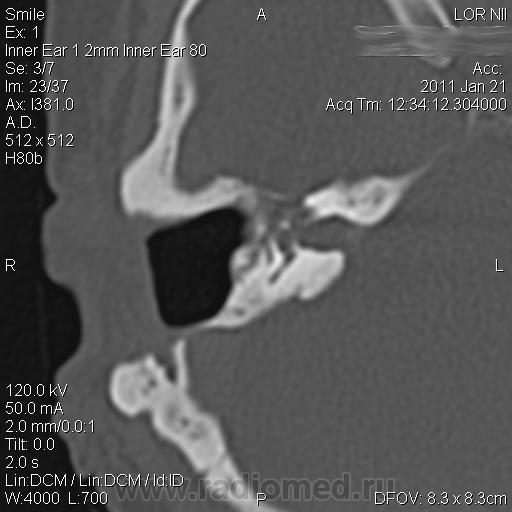

Пациентка Ш. 44 лет.

Из анамнеза: оперирована в 1982 году по поводу правостороннего острого гнойного среднего отита (Радикальная операция на правой височной кости).

Жалобы на тугоухость справа, периодические головокружения, боль в области правого глаза. В мае 2010 г возник парез лицевого нерва справа.

По данным МРТ, выполненной по месту жительства «Заключение: Интраканальное образование правого внутреннего слухового прохода».

Данные КТ прилагаются. 31-01-2011 выполнена операция - окончательный диагноз …? А Вы думаете какой…?

Ответ: Вторичная холестеатома, гистологически подтверждена

Нет не попутали. Присутствовали на операции и видели гистологию. Сами выбирали между шванномой и холестеатомой.